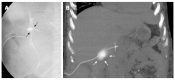

Orthotopic liver transplantation (OLT) represents a major treatment for end-stage chronic liver disease, as well as selected cases of hepatocellular carcinoma and acute liver failure. The ever-increasing development of imaging modalities significantly contributed, over the last decades, to the management of recipients both in the pre-operative and post-operative period, thus impacting on graft and patients survival. When properly used, imaging modalities such as ultrasound, multidetector computed tomography, magnetic resonance imaging (MRI) and procedures of direct cholangiography are capable to provide rapid and reliable recognition and treatment of vascular and biliary complications occurring after OLT. Less defined is the role for imaging in assessing primary graft dysfunction (including rejection) or chronic allograft disease after OLT, e.g., hepatitis C virus (HCV) recurrence. This paper: (1) describes specific characteristic of the above imaging modalities and the rationale for their use in clinical practice; (2) illustrates main imaging findings related to post-OLT complications in adult patients; and (3) reviews future perspectives emerging in the surveillance of recipients with HCV recurrence, with special emphasis on MRI.